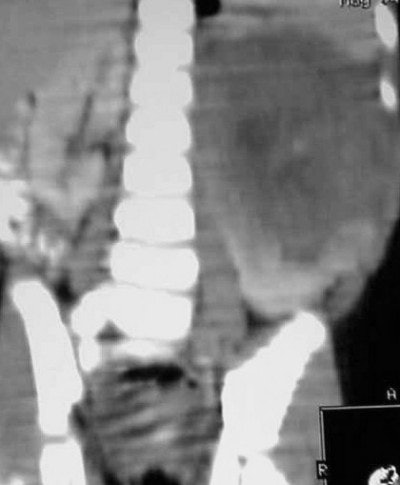

In Figure CT 9, the scout film shows a gaseous abdomen with displacement of bowel contents towards the right lower quadrant.

Axial images (Figures CT 10 and CT 11) show a mass beginning just below the kidneys on the left side and extending almost through the pelvis. The child was diagnosed with Wilm’s tumor of the left kidney.